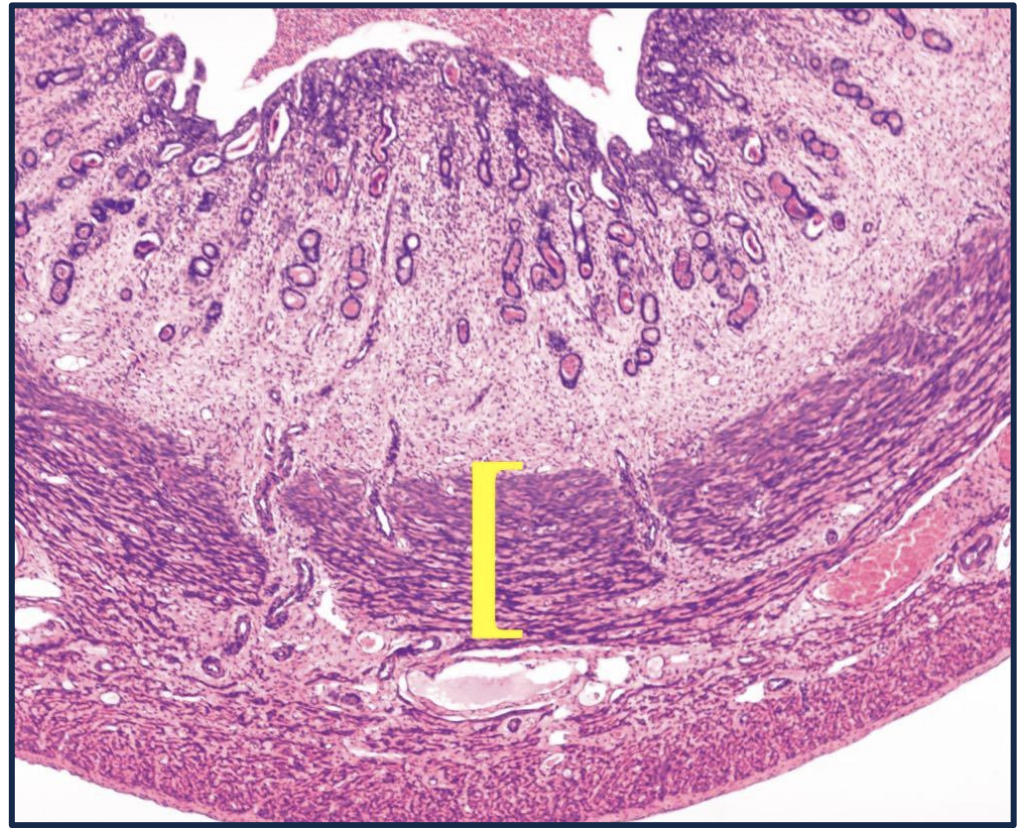

25

This region is called the _

This region is called the **squamocolumnar junction** * This is the most common location for cervical squamous cell carcinoma